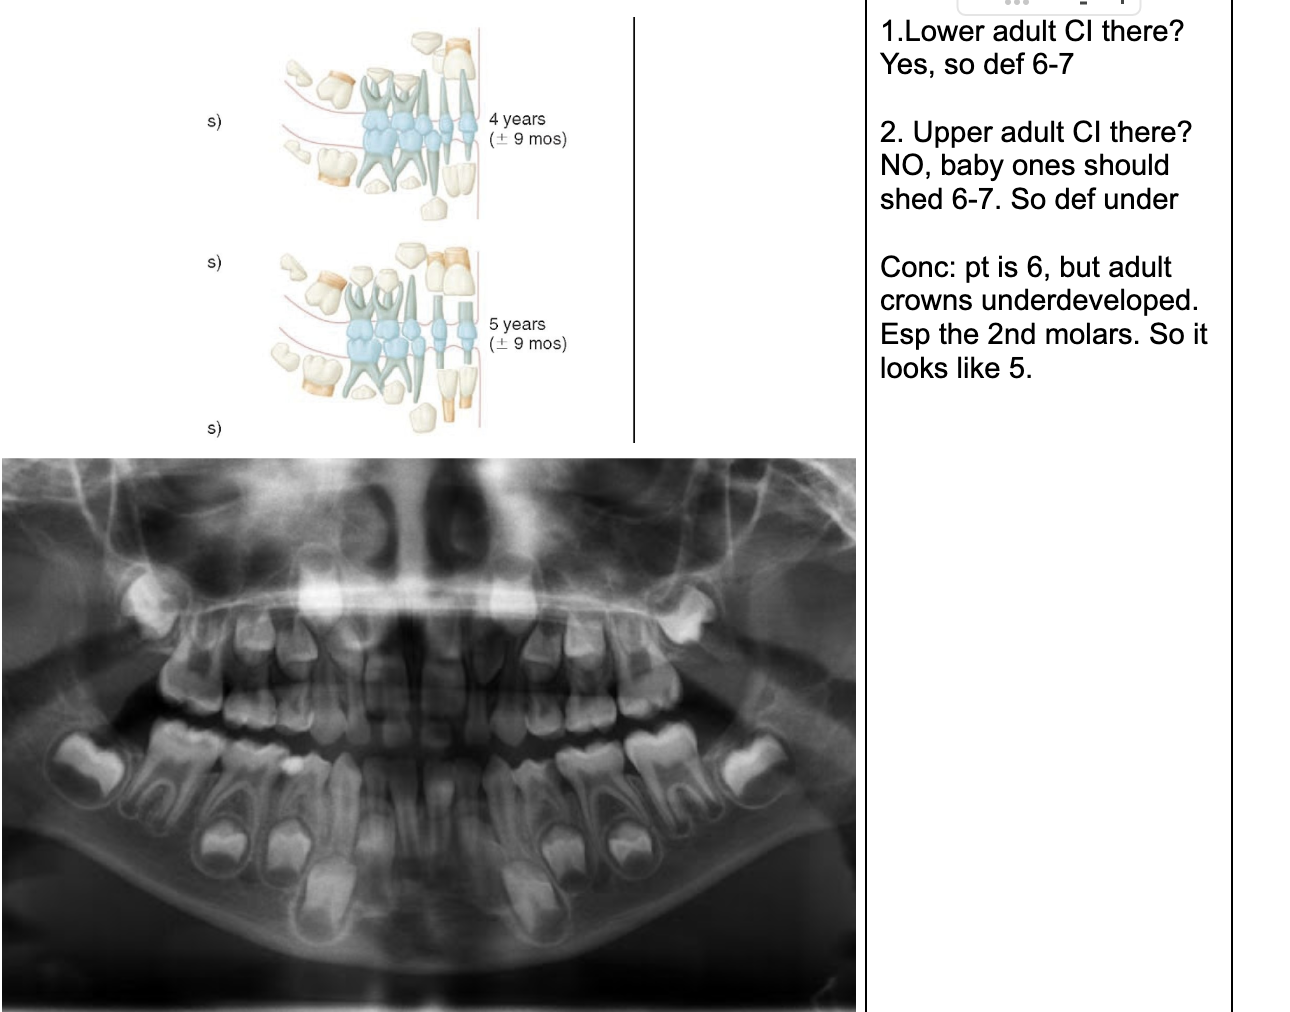

1.Lower adult CI there? YES. so def 6-7

1. Upper adult CI there (they normally erupt 7-8)? NO, baby ones should shed at 6-7.

Conc: pt. Is 6 y.o